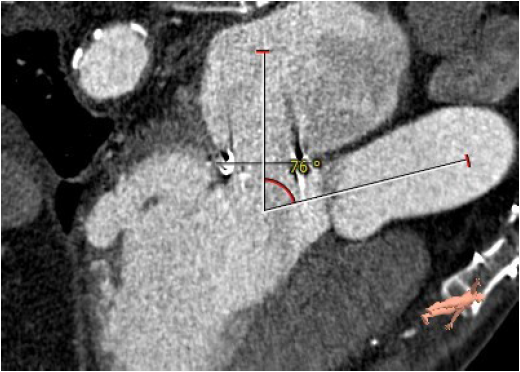

主动脉与生物瓣轴夹角76°

左室与生物瓣轴夹角145°